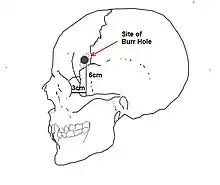

Inspired by the work of Italian psychiatrist Amarro Fiamberti, Freeman at some point conceived of approaching the frontal lobes through the eye sockets instead of through drilled holes in the skull. In 1945 he took an icepick[n 16] from his own kitchen and began testing the idea on grapefruit[n 17] and cadavers. This new "transorbital" lobotomy involved lifting the upper eyelid and placing the point of a thin surgical instrument (often called an orbitoclast or leucotome, although quite different from the wire loop leucotome described above) under the eyelid and against the top of the eyesocket. A mallet was used to drive the orbitoclast through the thin layer of bone and into the brain along the plane of the bridge of the nose, around 15 degrees toward the interhemispherical fissure. The orbitoclast was malleted 5 centimeters (2 in) into the frontal lobe, and then pivoted 40 degrees at the orbit perforation so the tip cut toward the opposite side of the head (toward the nose). The instrument was returned to the neutral position and sent a further 2 centimeters (4⁄5 in) into the brain, before being pivoted around 28 degrees each side, to cut outward and again inward. (In a more radical variation at the end of the last cut described, the butt of the orbitoclast was forced upward so the tool cut vertically down the side of the cortex of the interhemispheric fissure; the "Deep Frontal Cut".) All cuts were designed to transect the white fibrous matter connecting the cortical tissue of the prefrontal cortex to the thalamus. The leucotome was then withdrawn and the procedure repeated on the other side.